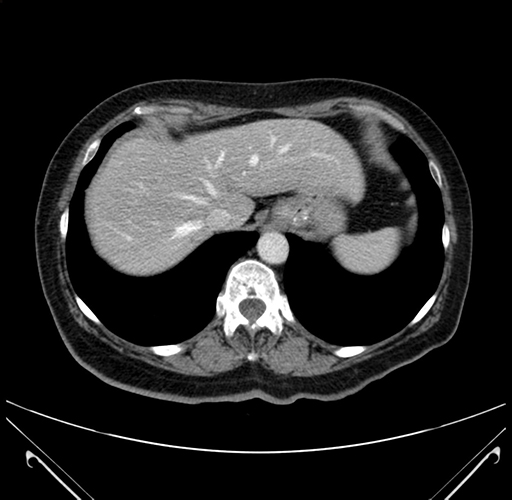

Pre-Chemo: Axial Venous

Axial Venous